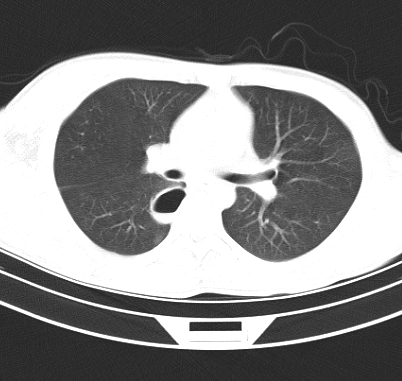

标题: CT19170:男 24岁,胸部外伤一周行CT检查 [打印本页]

男 24岁,胸部外伤一周行ct检查 未传纵隔窗

首先考虑肺裂伤形成的液气囊肿.纵膈胸膜包裹性的液气胸可能性小,病变主要在肺内.

考虑外伤肺撕裂致右肺下叶纵隔胸膜下液气囊肿。

结合临床考虑为右肺下叶背段撕裂伤后形成局限性包裹性的液气胸。